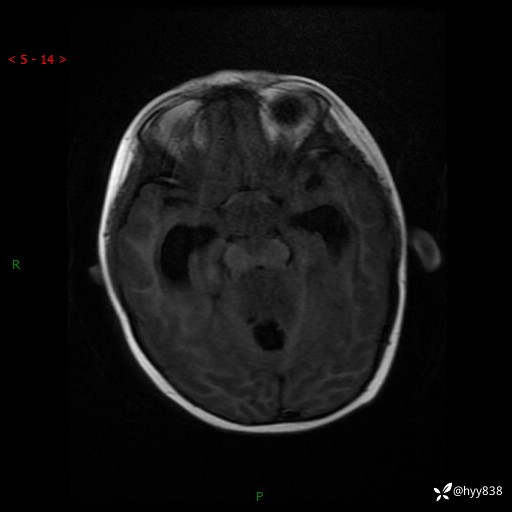

性别:女

年龄:3岁

简要病史:发现行走不稳2个月,加重1个月

颅脑MRI平扫+增强

三脑室、四脑室多发病变,如何分析?